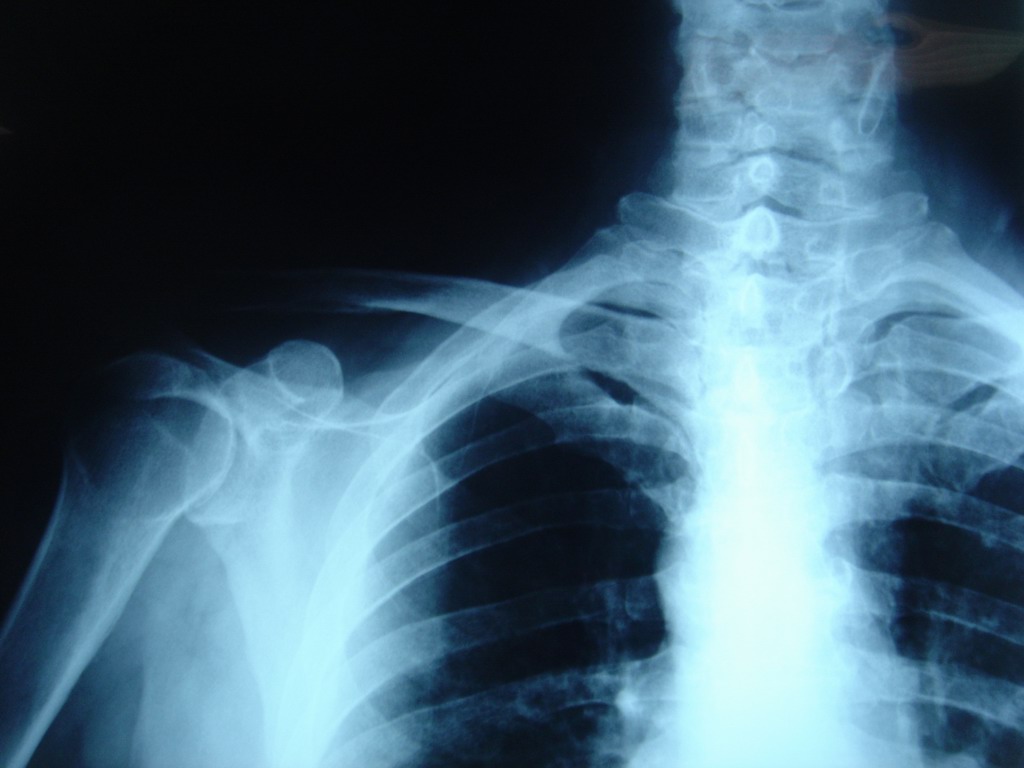

Torero y muy buen amigo de este equipo, que acude a nuestra enfermería aquejado de gran dolor en cuello con molestias y dolor en miembro superior derecho de carácter agudo que muchos días le imposibilitan su vida normal.

El cuadro tiene varios meses de evolución y según el torero comenzó hace mucho como consecuencia a cogida de toro con caída al albero “de mala manera” con el cuello en hiper extensión.

En las radiografías se advierten cambios degenerativos consecutivos a su edad y los repetidos traumatismos que sufren los toreros tanto en su mantenimiento físico como en los accidentes del ruedo.

Obsérvese el desalineamiento de las apófisis espinosas, los osteofitos, etc.

Diagnóstico.  Artrosis cervical